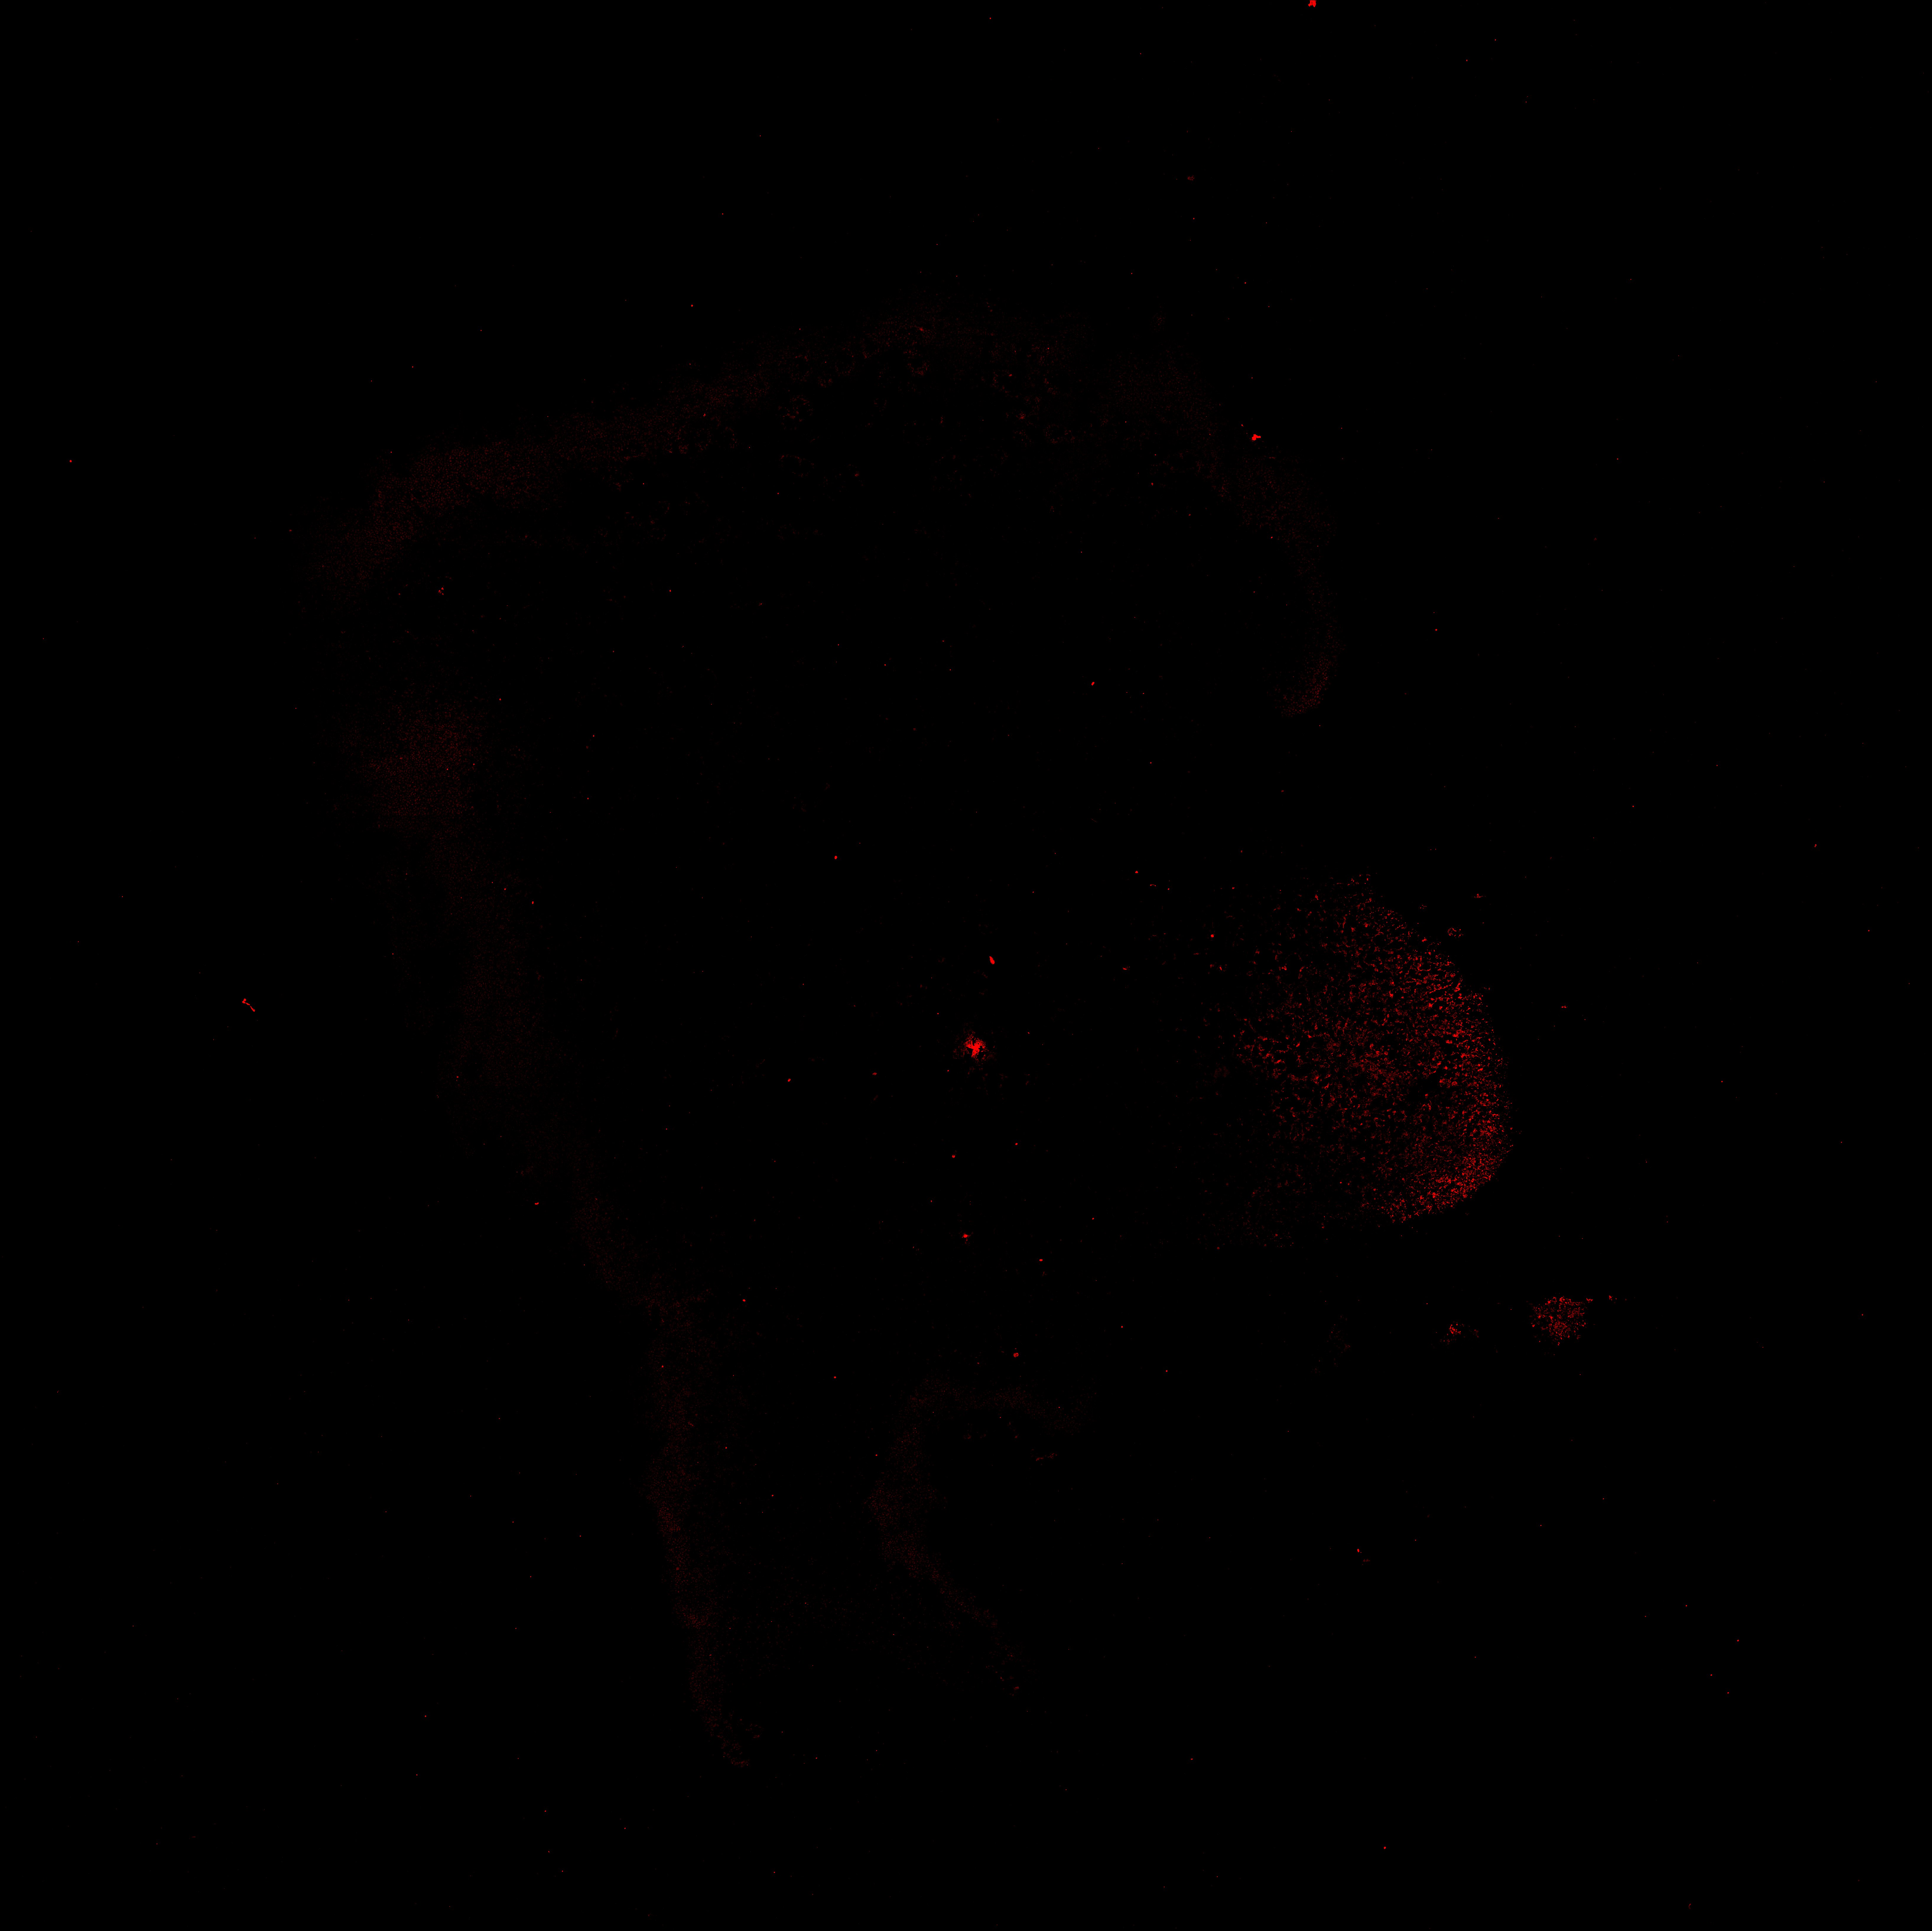

TH

19PCW human midbrain

22PCW human midbrain